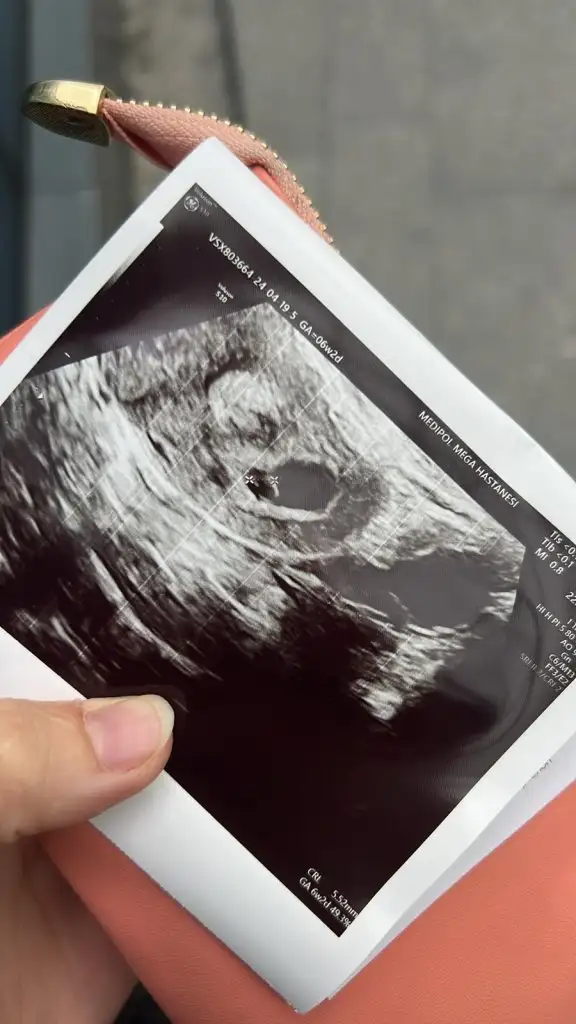

Bizede tahminde bulunur musunuz kızlar

Kıza benziyor 6 7 haftalık var mı foto